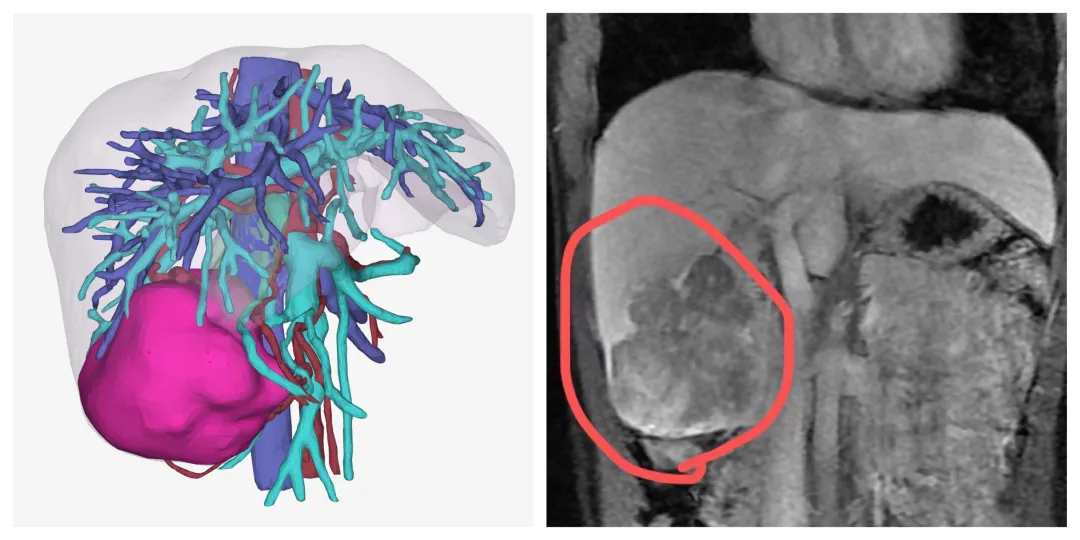

做了一系列检查,结果陆续出来:甲胎蛋白9612.000ng/ml;乙型肝炎表面抗原6110.000COI……磁共振扫描结果显示,肝右叶巨大肿块,周围散在结节状病灶。

▲三维重建和MRI影像图片

经过术前检查和周密计划,医生为她做了右半肝切除手术,用时约3小时,手术顺利。术后病理确诊为肝细胞性肝癌。